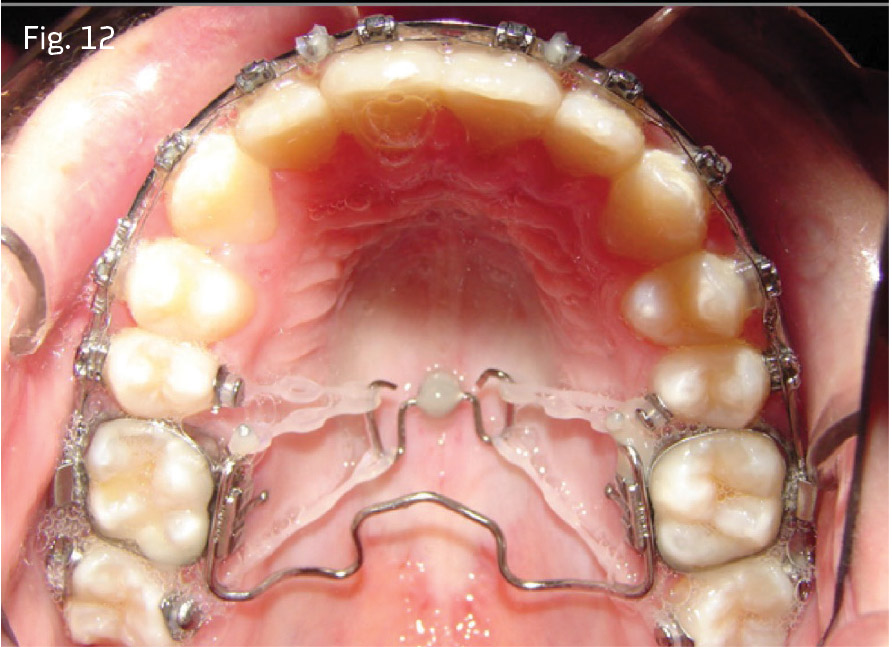

In both cases, passive self-ligating brackets with standard anterior torque prescription were placed. Quarter-inch, 2-ounce posterior cross-elastics were used as needed from the lingual of the upper molars to the labial of the lower molars from the first archwire insertion of .014 copper nickel titanium (CuNiTi). The archwire sequence of 14x25 unit, 18x25 CuNiTi, 19x25 stainless steel was followed with 10-week appointment intervals. The posterior crossbite relationships in Case 1 were corrected before advancement to 18x25 CuNiTi. In Case 1, once both arches were worked to 19x25 stainless steel, a Rocky Mountain Orthodontics fixed/removable transpalatal arch was inserted into the vertical lingual sheaths of the upper molar bands, with 6mm of clearance relative to the palate (Fig. 12). In Case 2, molar bands were avoided by placing a bonded TPA bent from .036 stainless steel. It was bonded to the occlusal surfaces of the upper first molars (see Fig. 13). This prevents lingual rolling of the buccal segments during intrusion.